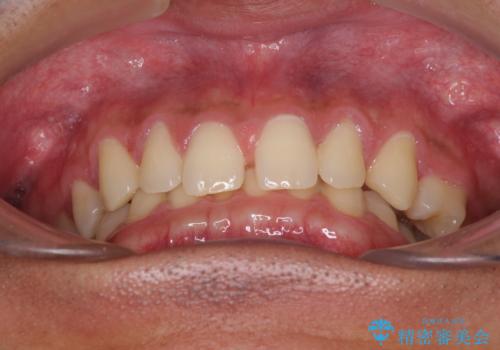

- 歯のデコボコと歯の隙間を気にして来院された患者様です。

隙間の原因は、埋伏や前後に重なってしまっている上顎小臼歯と、下の前歯が見えなくなるくらいのディープバイトで、それらを改善する必要がありました。